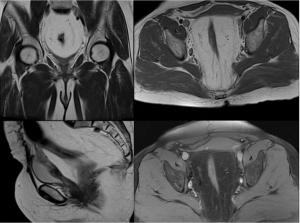

Image IQ: 45-year-old Woman, Nonspecific Pelvic Pain and Fullness

45-year-old woman with nonspecific pelvic pain and fullness, after MRI underwent cystoscopy and biopsy which revealed proliferative cystitis.